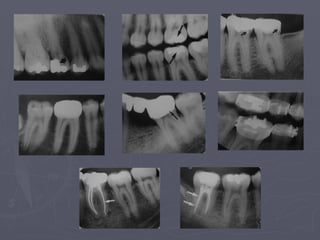

Teeth

► Teeth are composed primarily of dentin, with an

enamel cap over the coronal portion and a thin layer

of cementum over the root surface.

► Enamel cap appears the most radiopaque.

► Dentin is less radiopaque and is roughly comparable

to the bone.

► The enamelo-dentinal junction appears as a distinct

interface that separates those two structures.

► Cementum is not usually apparent.

• In a mature tooth, the shape of the pulp

chamber and canals may change, with aging

occurs a gradual deposition of secondary

dentin which begins apically, proceeds

coronally and may lead to pulp obliteration.

• Trauma to the teeth also may stimulate

dentin production.

► Caries, restoration, attrition or erosion may

cause pulp obliteration.

Cervical Burnout

► It is a diffuse radiolucent

areas with ill-defined

borders on the mesial or

distal aspects of teeth in

the cervical region

between the enamel cap

and the crest of the

alveolar ridge.

► It is not to be confused

with root caries.